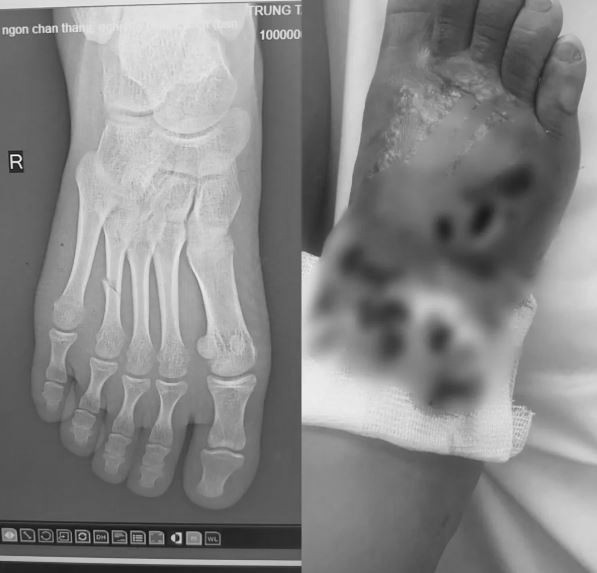

Bệnh nhi 14 tuổi bị gãy xương đốt bàn chân kèm nhiễm trùng nặng. Ảnh: BVCC.

Tại đây, kết quả chụp X-quang cho thấy bệnh nhi bị gãy xương đốt bàn chân, kèm theo nhiễm trùng mô mềm nặng. Các bác sĩ đã tiến hành điều trị kháng sinh liều cao, làm sạch ổ hoại tử và bó bột hở vùng tổn thương. Sau 1 tuần điều trị tích cực, tình trạng nhiễm trùng đã cải thiện, sức khỏe bệnh nhi dần ổn định.